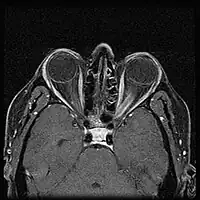

| Optic nerve sheath meningioma - Left eye esotropia and proptosis of left eye | |

When ONSM is suspected, MRI of the brain or orbits should be performed. This will usually show characteristic findings and confirm the diagnosis.[5]